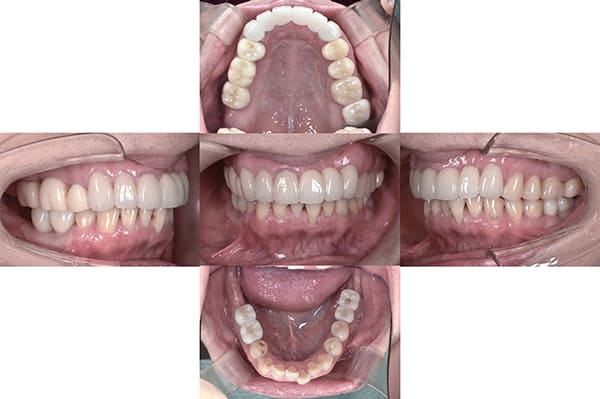

治療後の状態

こちらが最終的な補綴物が入った状態です。

見た目が大きく改善されたことで患者様もとても満足され、さらにしっかりと噛めるようになったことを大変喜ばれていました。